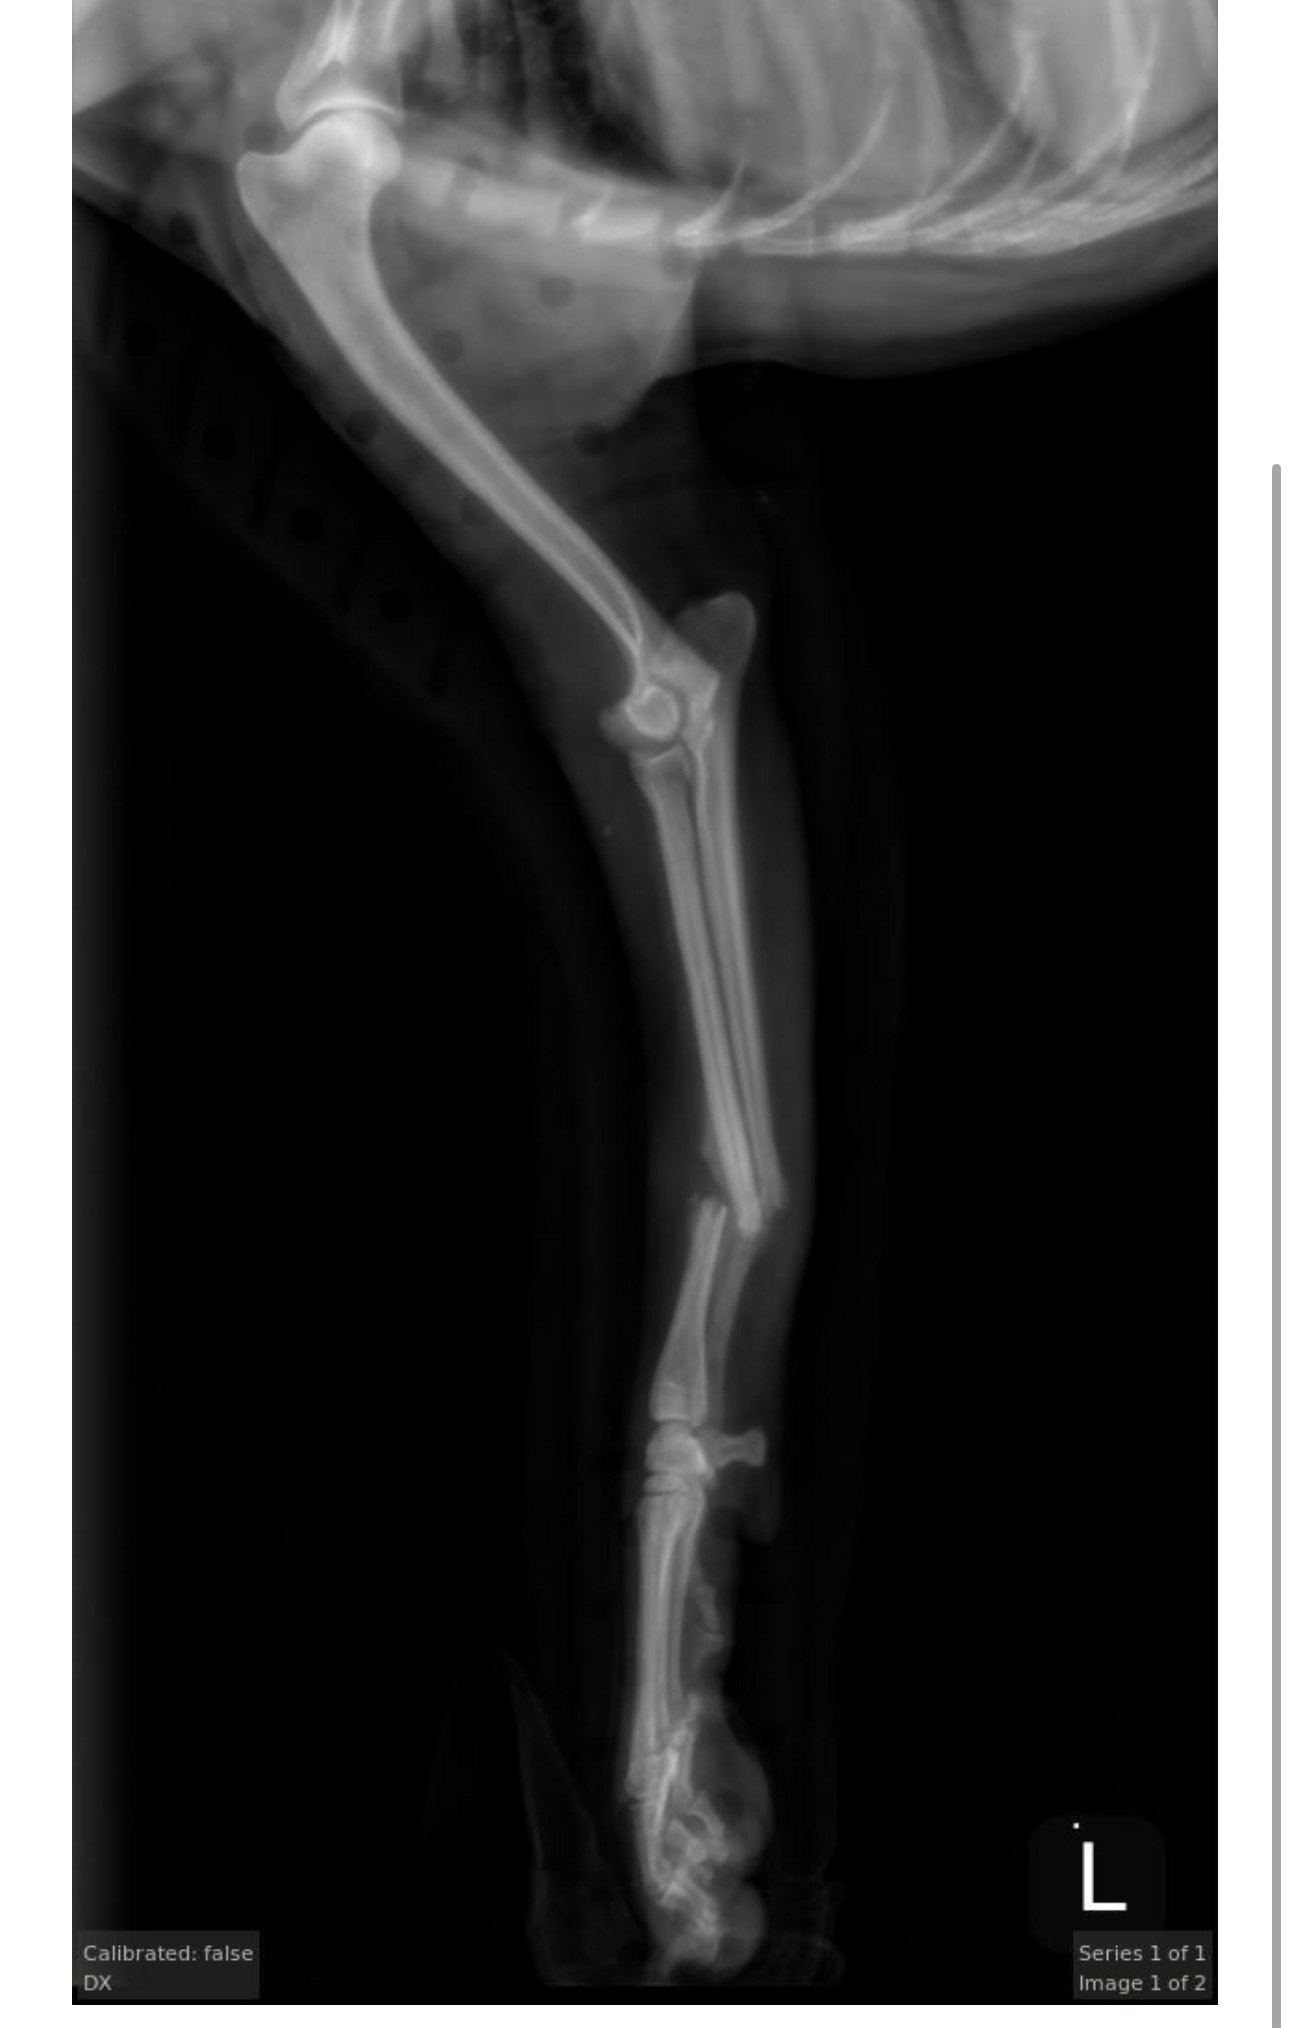

My sweet dog Yoshi recently broke his leg. I tried weekly splint changes and X-rays, hoping he could heal without surgery, but unfortunately it wasn’t successful. He now needs emergency surgery to recover and walk normally again.